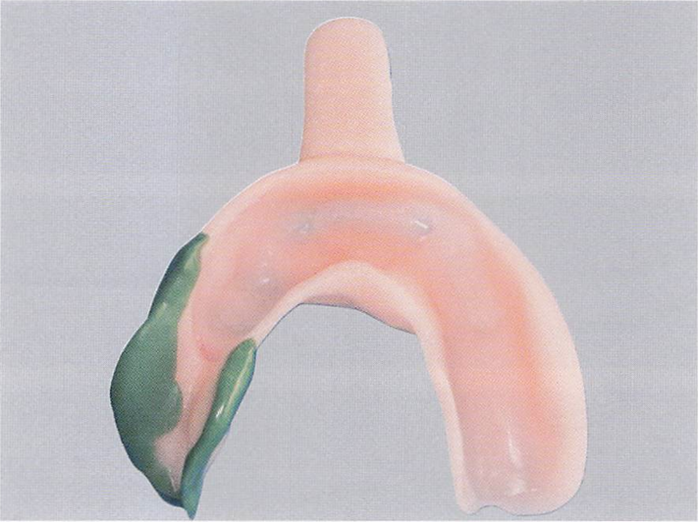

適合試験材を用いた部分床義歯内面の状態の写真を別に示す。義歯調整を行うことになった。

使用する器材はどれか。2つ選べ。

a.ロビンソンブラシ

b.シリコーンポイント

c.カーボランダムポイント

d.タングステンカーバイトバー

解答を見る

b.c